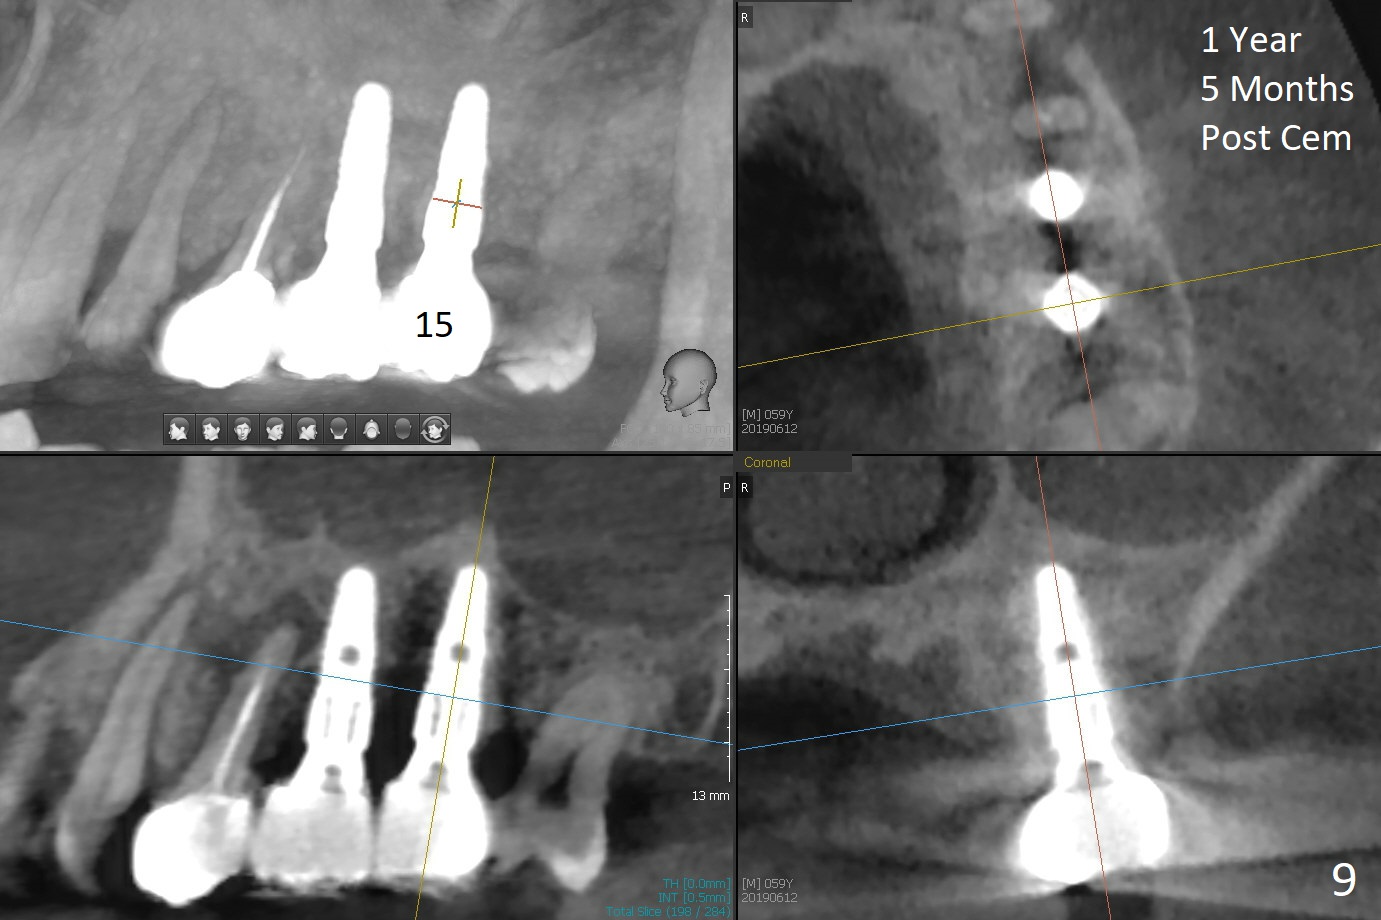

When 1.2 mm drill is used for osteotomy at #14 and 15, the bone feels to be soft (Fig.1). After change in trajectory (Fig.2), Expander 1 (Fig.3: E1, 1/1.6 mm) can be inserted at #14 and 15, while E2 (1.2/2.3 mm) cannot at full length at #14, suggesting hard bone. Osteotomy continues with drills until 4.1x14 mm, followed by insertion of E4 (2.4/3.7 mm) at #14, while osteotomy goes on until E3 (1.7/3.1 mm) at #15 (Fig.4). A 4.5x12 mm SM implant is placed with 50 Ncm (with insertion of a 5.8x4(2) mm abutment as a guide for #15 osteotomy, Fig.5). The apical portion of the osteotomy at #15 (Fig.5 red line) is finished with drills, leading to placement of a 4.5x12 mm implant (>50 Ncm) and 4.8x4(2) mm abutment (Fig.6). With bone density is more than 200 units, bone expansion appears to be not indicated. The patient returns for #13-15 crown prep 4.5 months postop (Fig.7). Abutments change to 5.8x5(3) and 5.8x4(3) mm at #14 and 15, respectively with mesial reduction of the tooth #16 (curved line) before impression. Minimal bone loss is observed 1 year 5 month post cementation (Fig.8,9), thanks to pre-existing wide bone.